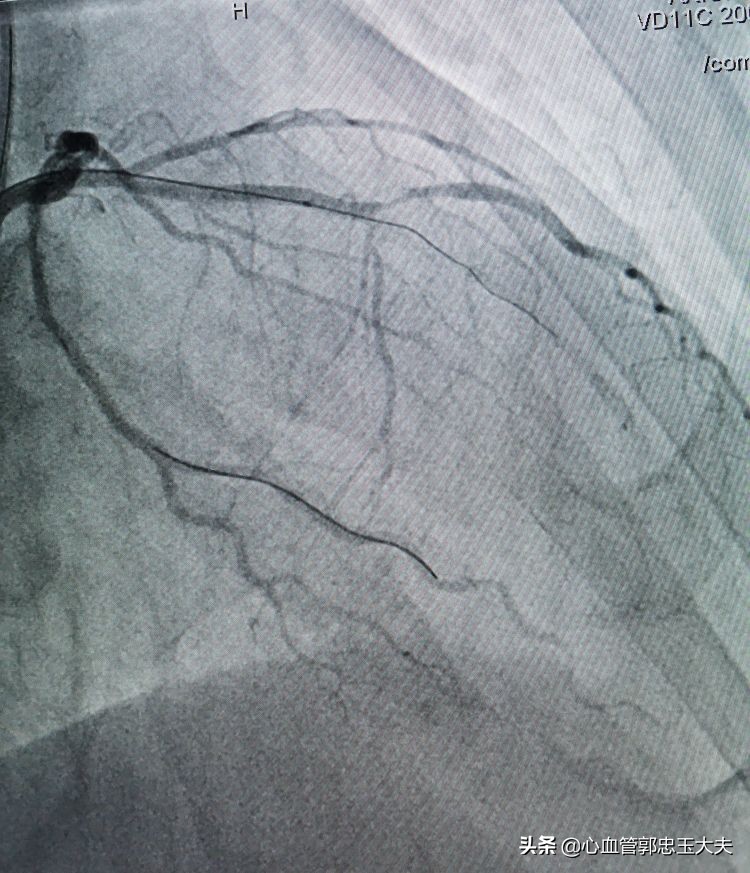

张大爷86岁了,有高血压病史,无烟酒嗜好。因为“反复胸闷头晕数月”入院。冠状动脉CTA示:三支病变,严重钙化合并高度狭窄。行冠脉造影示:前降支中远段钙化,完全闭塞,远端可见血管影。未见明显侧枝循环。(如下图)

回旋支近段远端85~90%狭窄(如下图)